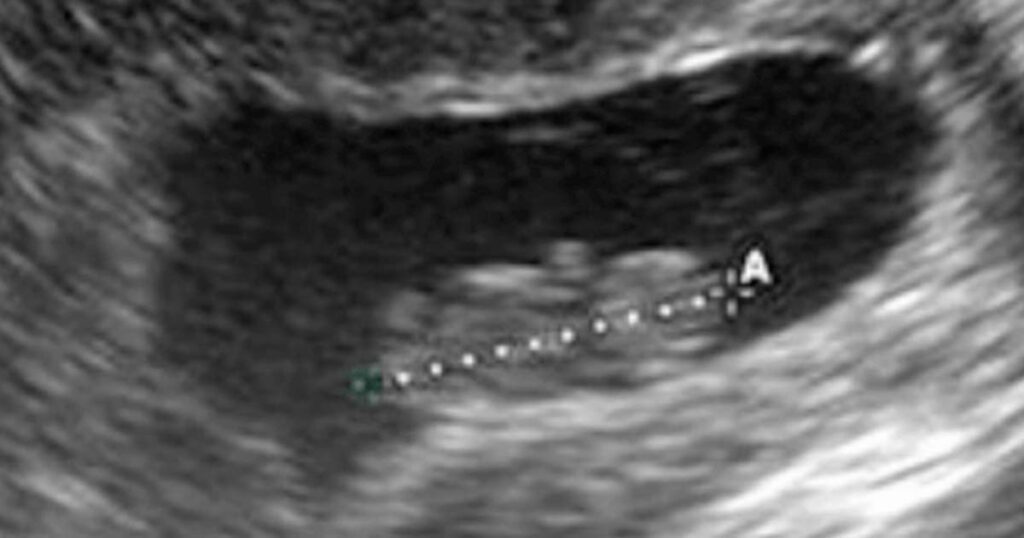

Läkarna var helt chockade, flickan var gravid i sjunde månaden och på väg att föda!